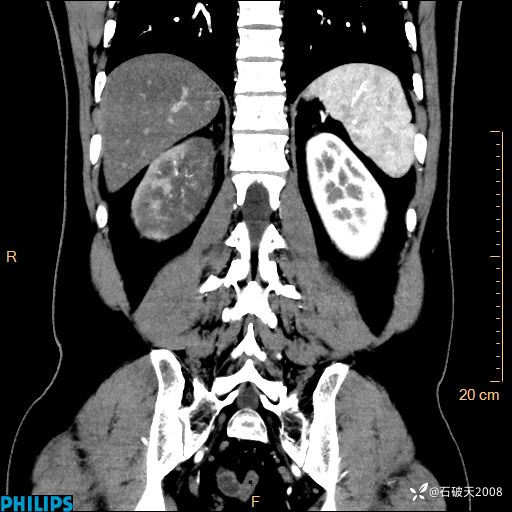

这个病例诠释了“腹部不增强,等于耍流氓”

男 44岁 主 诉:右侧腰背部疼痛4天。

现病史:4天前无明显诱因出现右侧腰背部疼痛,呈阵发性发作,疼痛性质描述不详,无尿频、尿急、尿痛,无恶心呕吐、腹泻、黑便,无胸闷、胸痛、呼吸困难,无发热、寒颤等,休息后缓解不明显,昨日到我院门诊就诊,行泌尿系彩超示:1.双肾肾砂;2.前列腺体积稍大。予“肾石通丸”、“左氧氟沙星片”等药物口服治疗后无缓解,昨日夜间再次到我院就诊,急诊科予“复方双氯芬酸钠注射液”肌注处理后好转,今晨仍感右侧腰背部疼痛,再次来诊并由门诊以“腰痛”为初步诊断收入我科。发病来患者神志清,精神稍差,饮食睡眠欠佳,小便正常,大便不畅,体重近期无下降。

冠状位